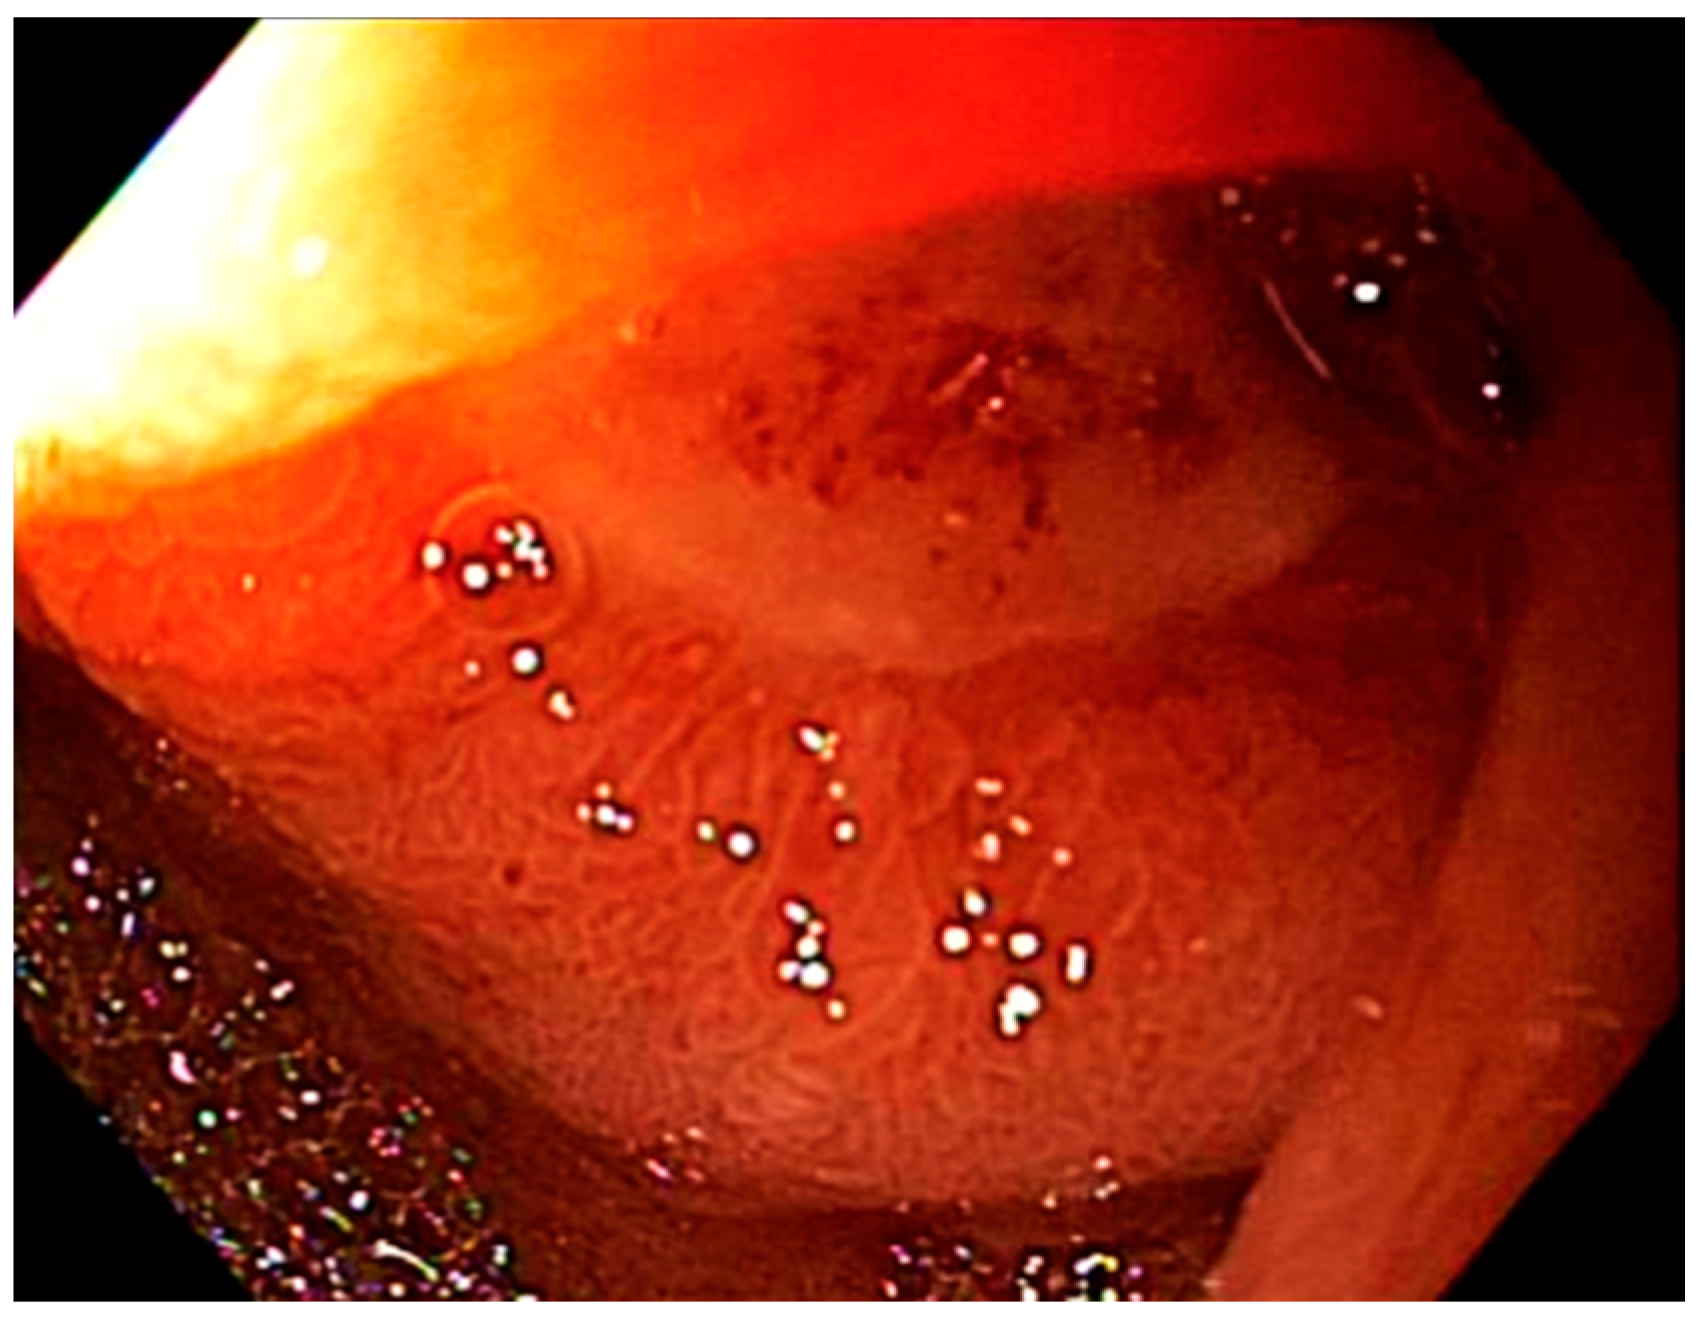

2.2. Toxicity Scoring

| Post-treatment (n = 17) | 5 (29) | 8 (47) | 4 (24) | 0 (0) |

| Post-treatment (n = 17) | 3 (18) | 11 (64) | 3 (18) | 0 (0) |